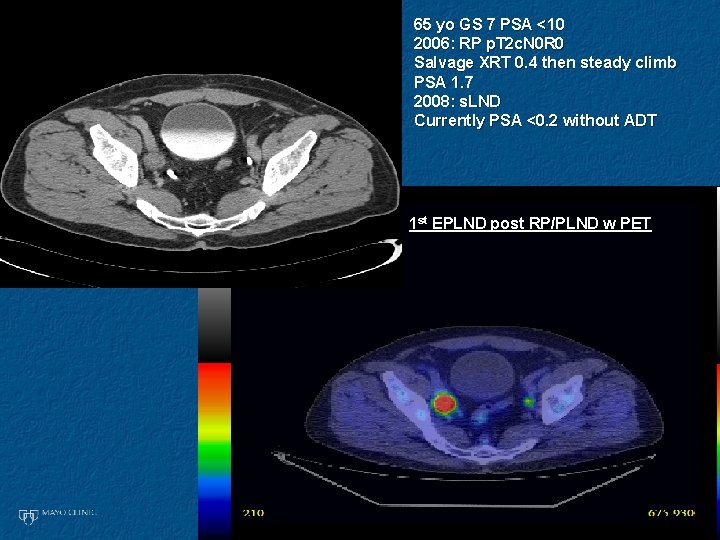

65 yo GS 7 PSA <10 2006: RP p. T 2 c. N 0 R 0 Salvage XRT 0. 4 then steady climb PSA 1. 7 2008: s. LND Currently PSA <0. 2 without ADT 1 st EPLND post RP/PLND w PET